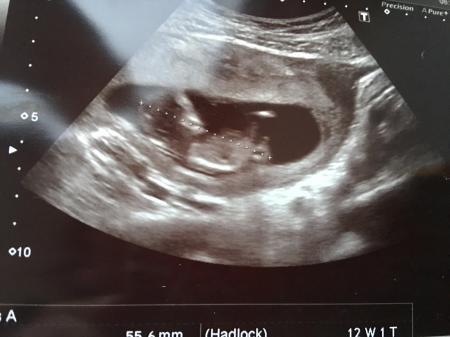

Guten Morgen. Das kleine Mäuschen ist schon so groß, dass mein Termin korrigiert wurde... der neue ET ist am 15.8. und somit ist die kritische Zeit schon vorbei. Heute wurde ganz viel gehüpft und gewunken. Montag gehts dann zum großen Ultraschall bezüglich Nackenfalte und Co, allerdings machen wir den Bluttest dazu nicht. Am Wochenende erfährt es dann auch unser 2 jähriger. Mal sehen was der sagt. Euch allen einen schönen Tag!!

Bild zu Zurück vom FA - Forum für August - Mamis